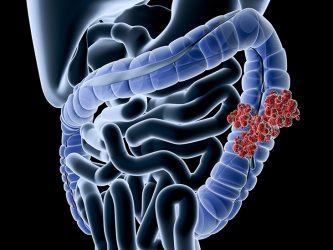

Mε τον όρο καρκίνος παχέος εντέρου εννοούμε το κακόηθες, εκείνο νεόπλασμα, το οποίο αναπτύσσεται στο παχύ έντερο ή στο ορθό. Ο καρκίνος του παχέος εντέρου είναι ένας από τους συχνότερους καρκίνους στον κόσμο.

Υπολογίζεται ότι πλέον των 300.000 νέων περιπτώσεων διαγιγνώσκονται κάθε χρόνο στην Ευρώπη. Αποτελεί το 3ο σε συχνότητα νεόπλασμα στις γυναίκες και στους άνδρες και τη 2η αιτία θανάτου από κακοήθη νεοπλάσματα.

Τα διάφορα στάδια του καρκίνου στο παχύ έντερο περιγράφονται με την επιστημονική ένδειξη Dukes:

• Dukes A -Ο όγκος εντοπίζεται μόνο στο εσωτερικό τοίχωμα του παχέος εντέρου.

• Dukes B -Ο όγκος έχει εισχωρήσει σε όλο το τοίχωμα χωρίς να προσβάλλει τους λεμφαδένες της περιοχής.

• Dukes C -Ο όγκος έχει επεκταθεί και σε ένα ή περισσότερους λεμφαδένες της περιοχής.

• Dukes D -Τα καρκινικά κύτταρα του όγκου έχουν διασκορπιστεί και σε άλλα όργανα του σώματος και έχουν δημιουργήσει δευτεροπαθείς όγκους (μεταστάσεις).